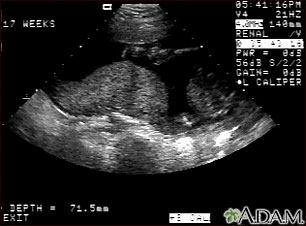

Ultrasonido normal a las 17 semanas de gestación que muestra la placenta durante una contracción normal, denominada contracción de Braxton Hicks, la cual es una de las contracciones que el útero experimenta periódicamente a través del embarazo para facilitar un mejor flujo sanguíneo hacia la placenta y el feto. En este ultrasonido la placenta aparece como un objeto con forma de montículo en el centro de la pantalla y puede observarse un objeto redondeado en la parte inferior de la imagen que corresponde a una vértebra materna. La placenta se ve mucho más aplanada cuando el útero no se está contrayendo.